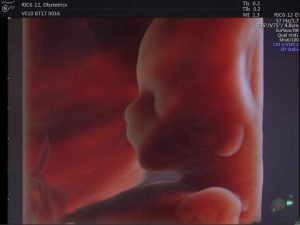

Siêu âm 4D giúp mẹ được nhìn thấy sự phát triển thai nhi và biết ...